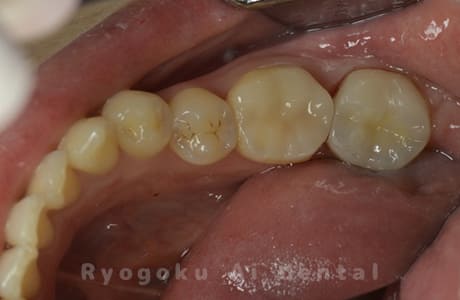

Case12

-

- 原因

- 慢性根尖性歯周炎

- 治療内容

- 再植歯根端切除術ならびにセラミック治療

- 治療費用

- 手術費:¥66,000

セラミッククラウン費:¥121,000

他院で行った根管治療後から歯茎の腫れが治らないとのことでご来院された患者様です。根管治療を再度行いましたが、腫れが治らないため、再植を行い、根尖部の病変ならびに根尖を切除し、逆根管充填を行い、戻しました。腫れも引き、経過良好です。

<リスク・副作用>

外科手術のため、術後に出血、痛みや腫れ、違和感を伴います。口腔内の状態によっては適応できないことがあります。歯根端切除で治らなければ抜歯を検討しなくていけない場合もあります。